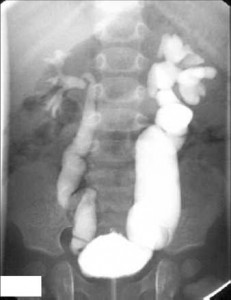

Sık idrar yolları enfeksiyonu geçiren çocuklarda ve cinsiyeti kız ise kesinlikle vezikoureteral reflü akla gelmelidir. Radyolojik olarak voidingsistouretrografi ile kesin teşhis konulur veya sintigrafi ile VCU yapılır. Derecesine göre Grade I, II, III ve IV şeklinde ayrılır.

Grade I; üreterin aşağısında sebat eden şişlik vardır.

Grade II; üreter boyunca dilatasyon vardır.

Grade IIa; dilatasyon yok fakat reflü böbreğin pelvisine kadar mevcuttur.

Grade IIb; pelvise kadar reflü vardır. Kalikslerde küntleşme vardır, dilatasyon yoktur.

Grade III; palvise kadar reflü, üreterde dilatasyon, kalikslerde küntleşme vardır, tortysite yoktur.

Grade IV; hem hidroüreteronefroz, hem de tortysite vardır.